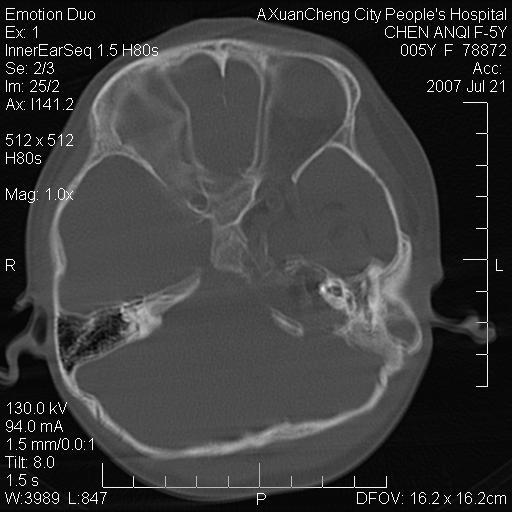

标题: PED0273:5岁,左耳流脓痛疼一周,颅底骨质破坏 [打印本页]

标题: PED0273:5岁,左耳流脓痛疼一周,颅底骨质破坏

患儿5岁,左耳流脓痛疼一周,左外耳道肉芽组织填塞 软组织窗显示病灶内结节状低密度影为气体密度

考虑中耳乳突炎并胆脂瘤形成可能。

左侧中耳炎并胆脂瘤,左颞骨岩部骨质破坏并颅内感染积气。

考虑化脓性中耳乳突炎伴胆脂肪瘤形成并左颞叶感染,不除外合并嗜酸性肉芽肿.